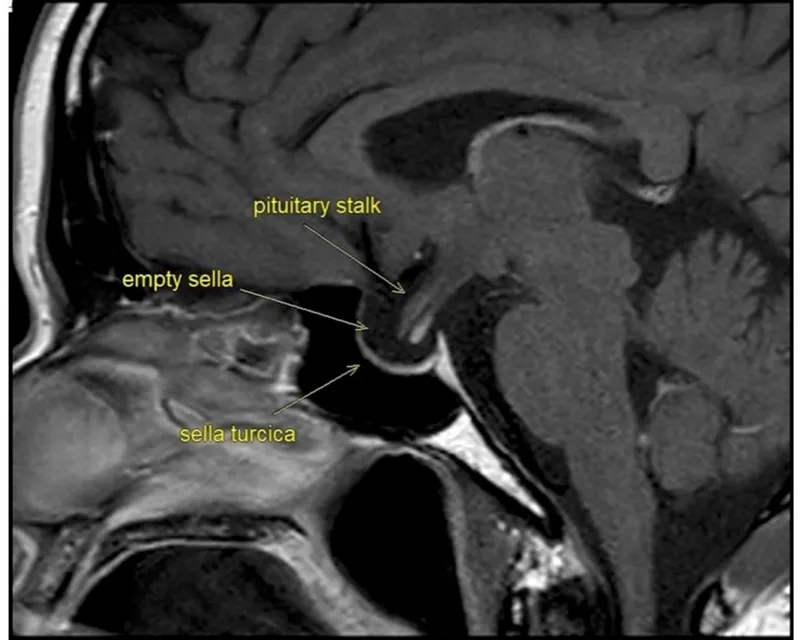

- Diagnosis: Low basal hormone levels (e.g., 8 AM cortisol, TSH, free T4) plus stimulation tests (e.g., ACTH stimulation test). Pituitary MRI to identify the cause.

- Etiology: Most commonly due to non-functioning pituitary adenomas. Other causes include Sheehan syndrome (postpartum necrosis), apoplexy (hemorrhage/infarction), iatrogenic (surgery, radiation), and infiltrative diseases (e.g., sarcoidosis, hemochromatosis).